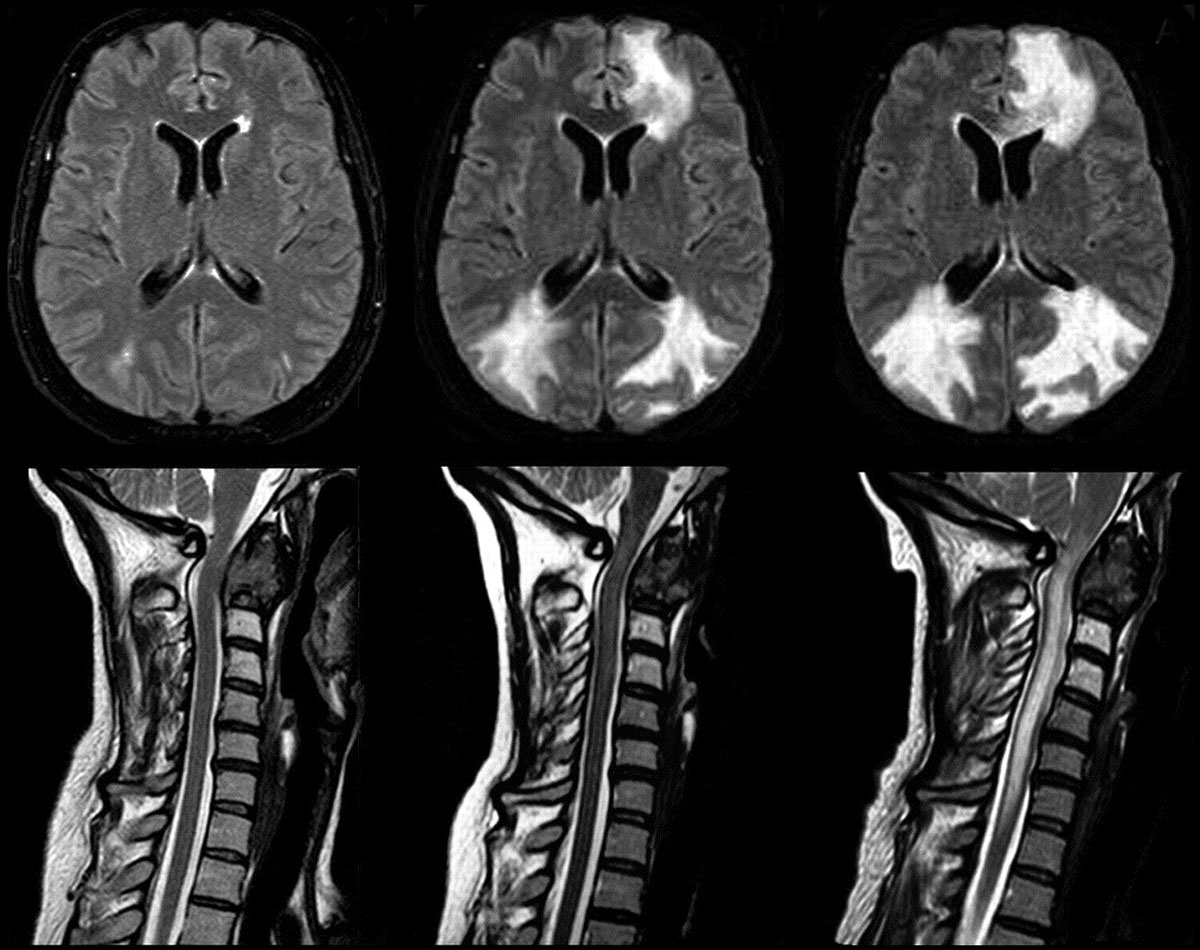

Диагностические процедуры должны проводить квалифицированные специалисты. Сначала рекомендуется обратиться к терапевту, который направит пациента к неврологу для назначения необходимых обследований. Для определения наличия патологии используются следующие методы:

- МРТ головного мозга — исследование, использующее электромагнитные волны для получения изображений;

- рентгенография — позволяет оценить состояние костных структур шеи и головы;

- КТ — наиболее точный метод для выявления заболеваний, основанный на послойном сканировании тканей.

Только после установления диагноза врач сможет назначить лечение, учитывая тип заболевания и причины его развития.